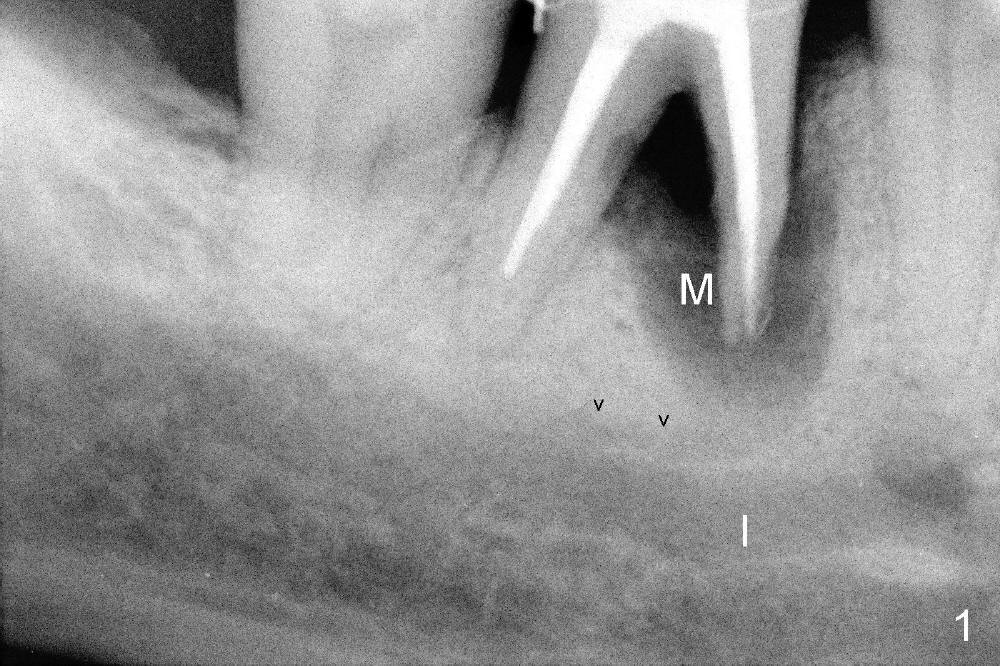

The tooth #30 of a 64-year-old man has endo failure with large radiolucency in the mesial socket (Fig.1 (PA), 2 (CT)). The tooth is nonsalvageable. The mesial lesion is closer to the inferior alveolar nerve (I/IAN) than the distal apex. In addition, there is a connection (Fig.1,2 arrowheads and Fig.2 insert pink dashed line) between the mesial lesion and the nerve. What is the connection, as related to extraction and immediate implant?